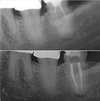

Cas clinique

Découvrez nos réussites à travers des radios de cas cliniques réalisés par notre cabinet d’endodontie